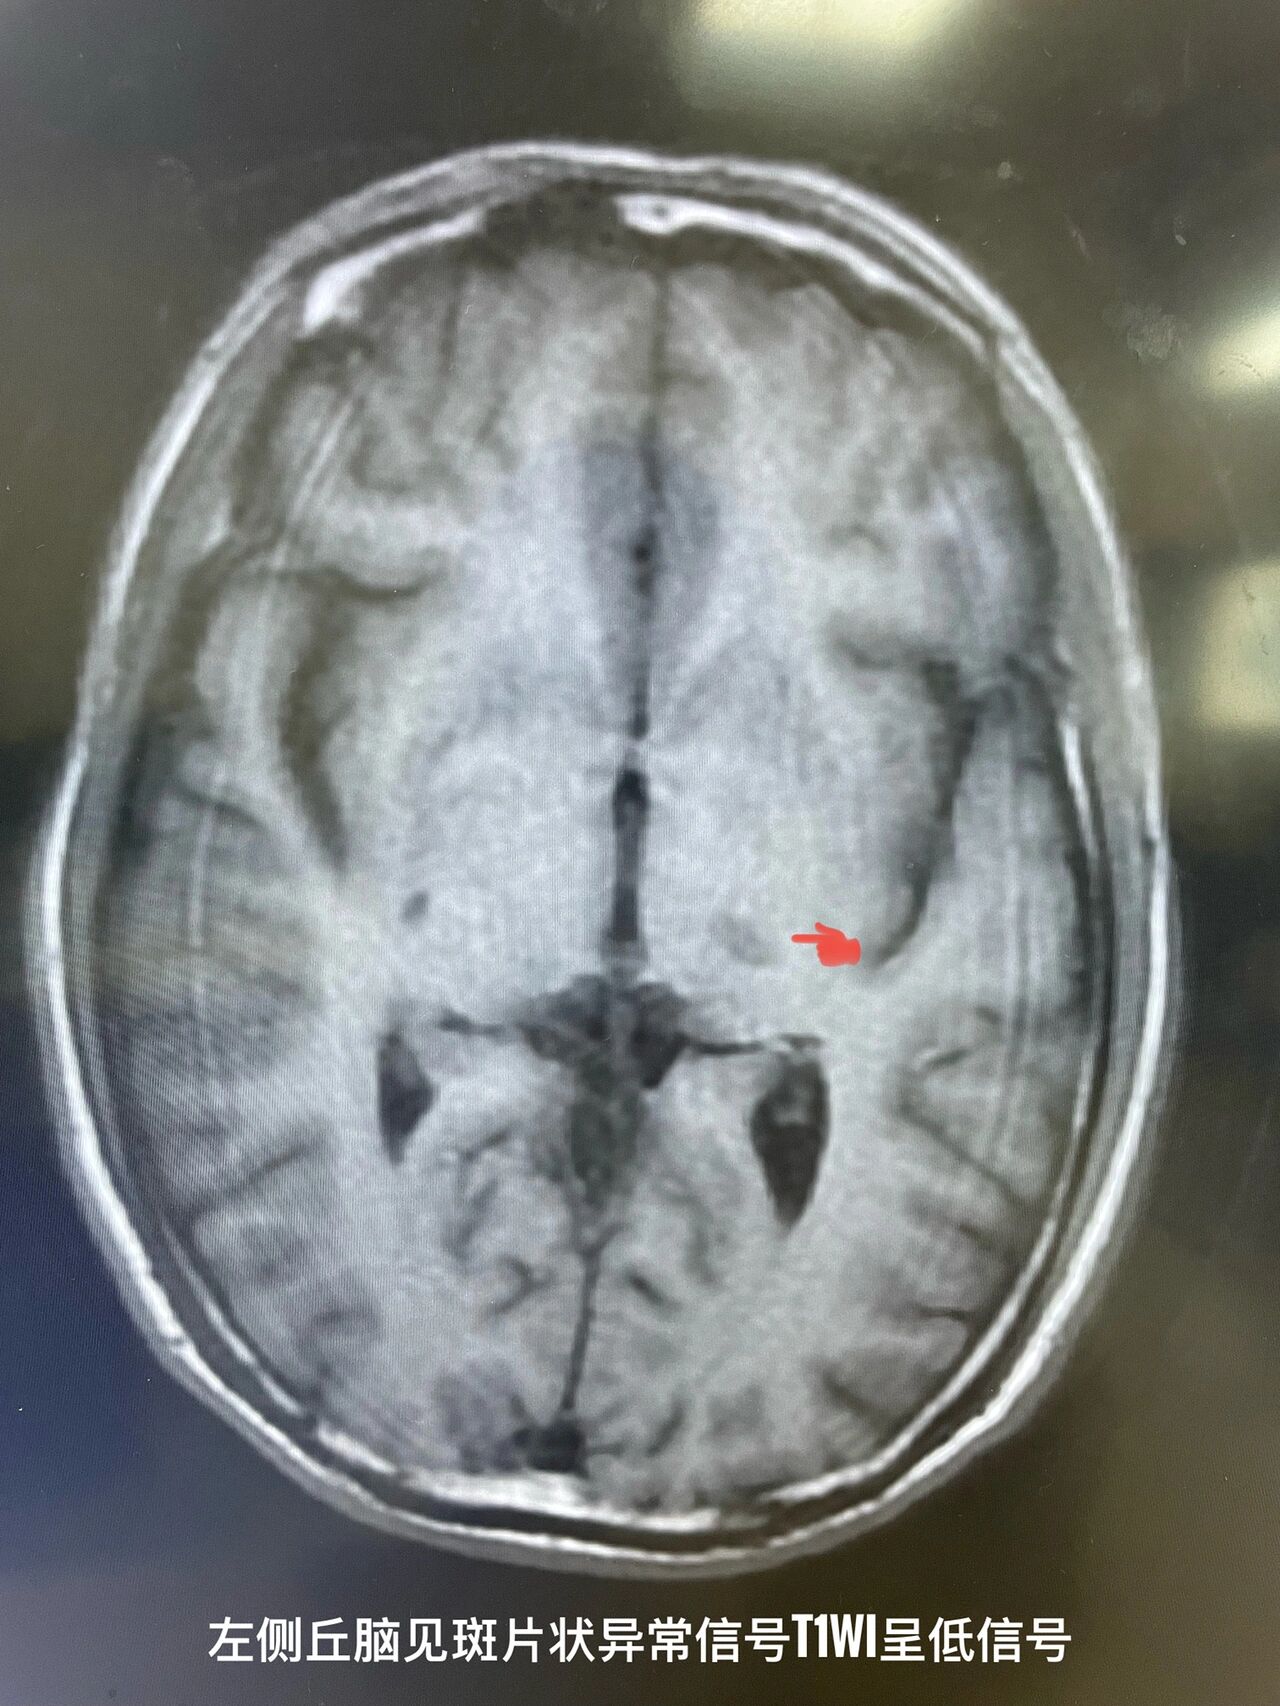

30岁脑梗